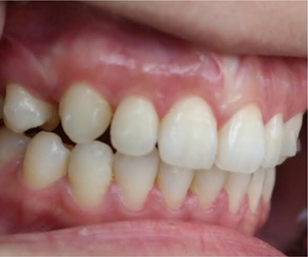

黄医生粗略的看了我的牙齿之后,说我存在两个问题,一个是开咬合(也就是后牙咬紧的时候上下牙之间还有差距),另一个是过咬合(后牙咬紧后上排牙比下排牙突出)。不夸张的说,那个前后差距我能放一根手指!

黄医生说我所有关于咬不开包装袋,嘴闭不上,睡觉呼吸方式,流口水,磨牙,右边咬肌突出,都是因为我的咬合完全不正确。过咬合和深咬合是很多亚洲人都有的问题,但是开咬合却不常见,要把我这“祖传”的嘴突治好,得靠改变我门牙和premolar的角度,然后整个上排往里推,牙齿的移动带着牙骨往里收,我的侧面会有很大的改善,我这种情况需要拔牙,但是智齿没有什么关系,一颗长出来了挺正,另外两颗深埋在牙床里离神经很近,取出来不但费很大功夫,还要冒脸瘫的风险,对我实际上没有任何影响。

有图有真相

3.15是我安装牙套的第一天,到10.16号已经整整七个月了,不管是牙齿上的改变,和脸部的改变都还蛮大的,许久不见我的朋友都会觉得我变了个人,也很多人说我脸瘦了,其实人家不是胖啦,只是肉很多!不多说,上图

其实还有20个牙套,但是我的凸牙已经基本上都回去了,改变巨大。下面放羞羞的真人图。

2017.03.15

2017.08.02

2017.10.17

比较明显的是我的人中明显变长,嘴突有了很大改善,下巴也因此显得更长,我发现最惊喜的改变是,我的肉肉脸!!!没有了!!!